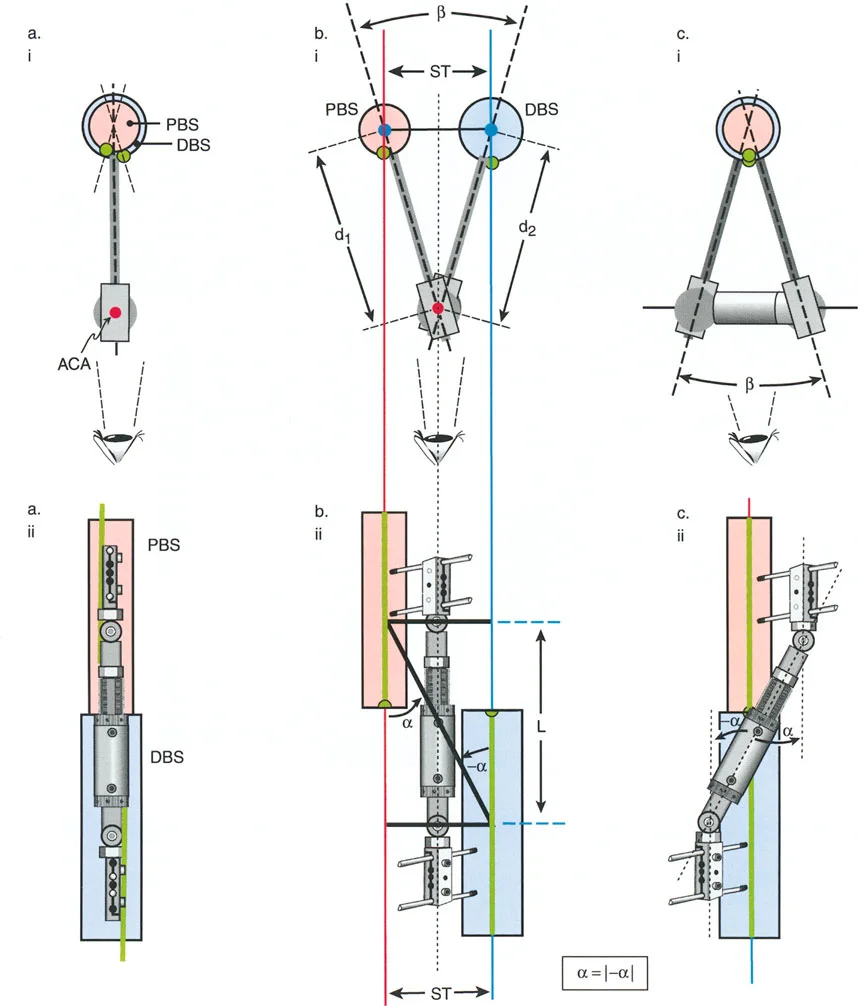

إتقان معدلات الشد: قاعدة المثلثات المتشابهة

القاعدة الذهبية البيولوجية لتوليد العظم بالشد، التي وضعها إليزاروف بعد عقود من التجارب على الحيوانات والبشر، هي معدل شد يبلغ 1 ملم يوميًا. يتم تقسيم هذا عادة إلى زيادات قدرها 0.25 ملم كل 6 ساعات لمحاكاة النمو المستمر للوحة النمو.

ومع ذلك، فإن الخطأ الشائع، الذي قد يكون كارثيًا أحيانًا للجراحين المبتدئين، هو سوء فهم أين يجب أن يحدث هذا الـ 1 ملم يوميًا.

معدل 1 ملم/يوم ينطبق بشكل صارم على القشرة المقعرة للعظم في موقع قطع العظم (الحافة الأمامية للإسفين المفتوح). نظرًا لأن الجهاز (قضيب الشد أو دعامة TSF) يقع على مسافة من العظم، خارج غلاف الأنسجة الرخوة، فإنه يتحرك على طول قوس أكبر بكثير. إذا وجهت المريض لشد القضيب بمعدل 1 ملم يوميًا، فإن العظم الفعلي سيُشد بجزء ضئيل من هذا المعدل، مما يؤدي إلى التصلب المبكر لموقع قطع العظم.

حساب معدل الشد الحقيقي

لحساب المعدل الصحيح للشد عند المفصلة، نستخدم قاعدة المثلثات المتشابهة، والتي تعتمد أساسًا على القاعدة الهندسية للدوائر متحدة